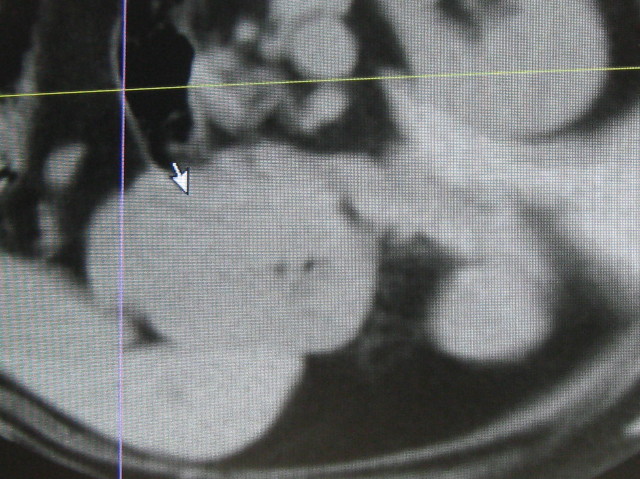

指先の平ぺったいのは腸壁(たぶん)

指の上の卵形は腎臓。

指の左の、空豆みたいな大きいのが発見された【腫瘍】

腫瘍の下は脾臓。

ポイントされている部分は、エコーで確認された脾臓のうっ血?みたいな部分。

ポントされている大きな白いかたまりが発見された腫瘍。